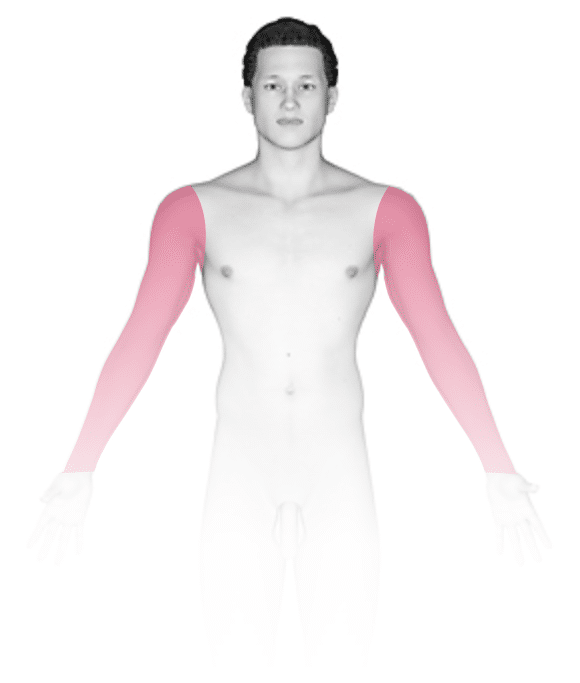

The most common locations for herpetic whitlow include:

- Thumb

- Index finger

- Other fingers